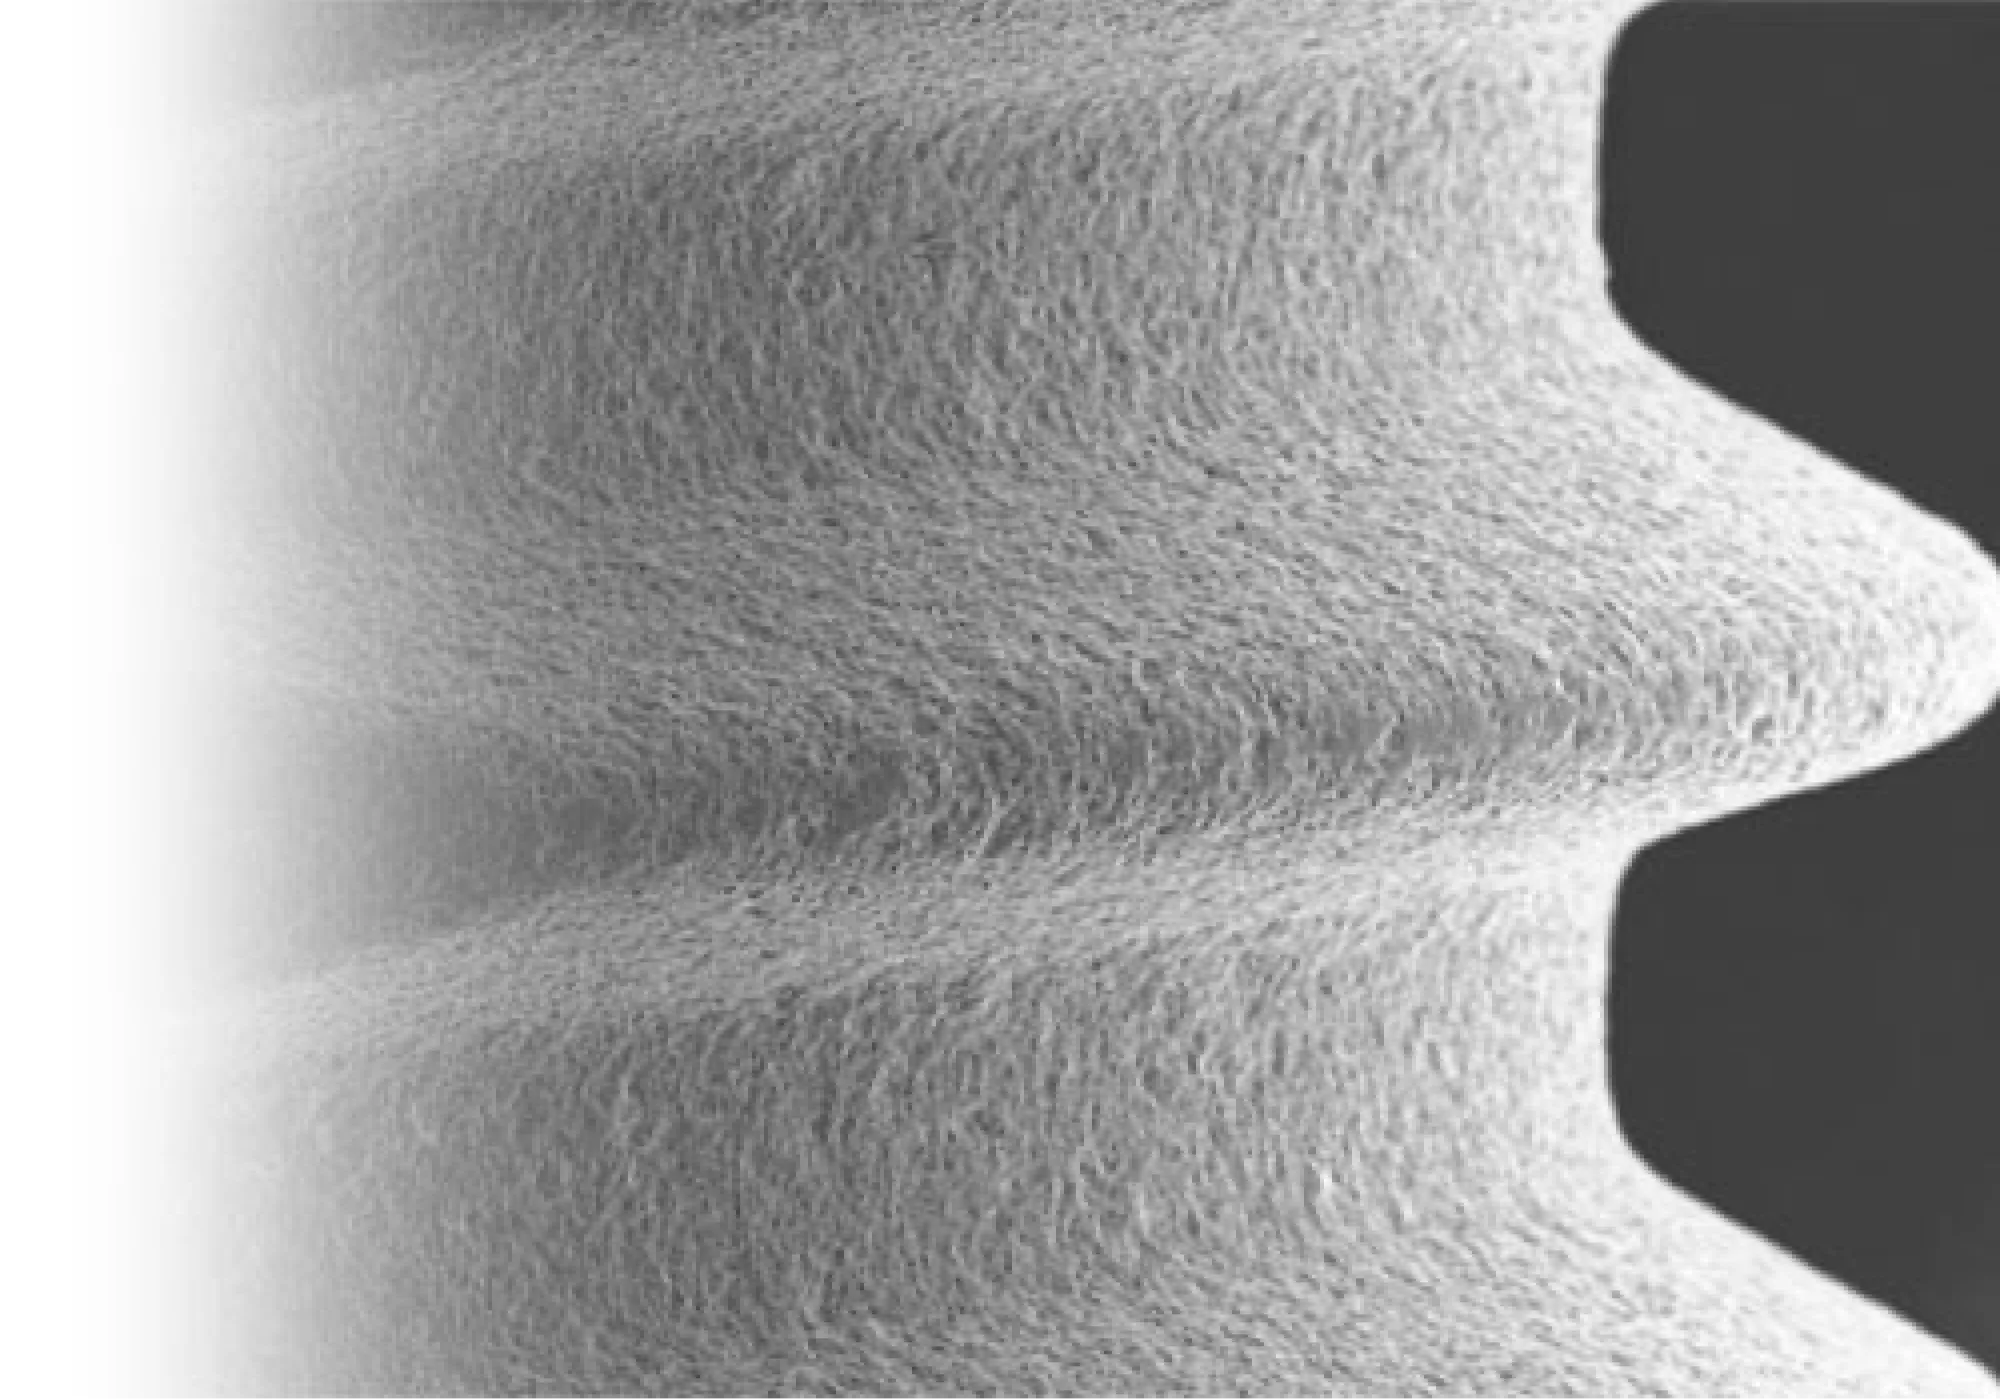

ネオスインプラントはイギリスに本社を持つネオス社というインプラントメーカーが、スウェーデンのイエテボリ郊外で開発、製造しているインプラントです。 このインプラントは、2000年にネオス社が創立されて以来販売され始めた新しいインプラントにも関わらず、たちまちインプラント先進国の間で一 流インプラントとして位置づけられました。 インプラントメーカーにはいくつか名だたる一流メーカーが存在しますが、そのような歴史の長いメーカーともはや同レベルに評価されているネオスインプラントには、いくつか突出した素晴らしい点があります。 また、このインプラントは企業主導ではなく、イエテボリ大学という教育機関で研究されていることも、多くの歯科医師から大きな信頼を得ている理由となっています。当院では、「自分が処置されてもよいと思えるインプラントを使いたい」という思いから、このネオスインプラントを取り入れています。 ネオスインプラントは、インプラント体表面が水になじみやすいよう、「エレクトロウェッティング」という技術を採用しています。 そのため、インプラントを埋め込んだ後、表面上で血液や、その成分の浸透によるタンパク質や生体分子がインプラント表面によく密着し、インプラントのねじの深部まで骨の形成が促進され、しっかりと初期に固定されます。 インプラント表面に施されている粗面化処理(表面を粗くする処理)によっても、骨と接触する表面積が増し、より強力な結合が得られるようになっています。 この処理はインプラントの歯根部分にはより粗めに、歯茎に近い部分にはよりマイルドに仕上げることにより、インプラント周囲炎を起こしにくいようなエ夫がなされています。 インプラントの素材はチタン製がほとんどですが、純チタンのもの、純チタンでないものなど様々なものが存在します。ネオスインプラントは、特別な製造 法により、チタンの純度を変えることなく、商業用純チタングレードIVを超える強度の強化チタンとなっています。 これにより、インプラントの破折のリスクを大幅に減らすことができます。また、純チタンであることにより、金属アレルギーのリスクも大幅に減らすことができ、金属アレルギーが心配な方にもより安心してお使いいただけます。 ネオスインプラントは、通常だと初期固定が得られないような、骨の質があまり良くない部分にでも対応できるという強みがあります。つまりどんなに骨の状態がやわらかすぎても、硬くすぎても対応できるようになっています。 その秘密として、まず、優れたドリルシステムが挙げられます。ネオスインプラントのドリルシステムは、インプラントを埋める穴を正確な位置に開けるのが容易なシステムになっています。 また、ネオスインプラント独自のTCFという二重構造のネジの形状のデザインにより、あらゆる骨質において、確実に安定が得られるようになっています。ネジはインプラントの先端にまで及んでおり、骨内での安定性をさらに高めて くれます。 LMGでは実際に当院で行ったインプラント手術の症例を公開しております。歯を失ってしまった方や、歯周病等で歯を残すことが困難と診断された方は当院でのインプラント治療なら綺麗で咬みやすい口腔内を取り戻すことができるかもしれません。ぜひチェックしてみてください。ネオス(NEOSS)インプラント

骨とインプラントの初期固定がしっかりと得られる

インプラント周囲炎を起こしにくい素材